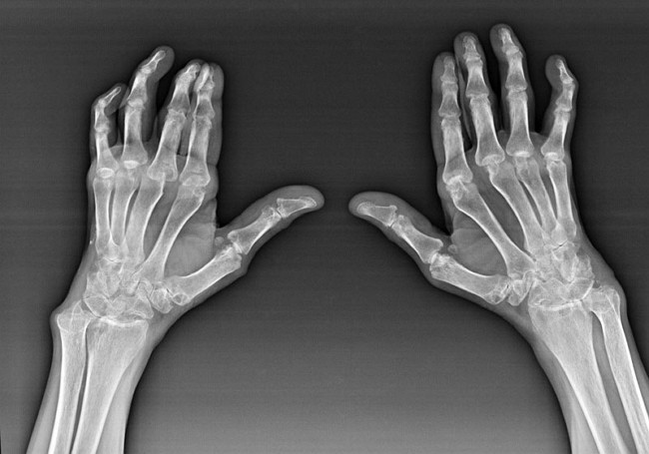

Rheumatoide Arthritis

Rheumatoide Arthritis ist eine Krankheit, bei der das menschliche Immunsystem das eigene Gewebe des Körpers schädigt. Mit anderen Worten, rheumatoide Arthritis ist eine Autoimmunpathologie. Diese Krankheit ist auch systemisch, da viele Gewebe davon betroffen sind ((Muskeln, Gelenke, Gefäße usw.) und Organe (Herz, Nieren, Lungen usw.) im Körper.

Trotz der Tatsache, dass rheumatoide Arthritis eine systemische Krankheit ist, leiden die Gelenke in größerem Maße, während die Läsion anderer Gewebe und Organe im Hintergrund steht. Mit dieser Krankheit können fast alle Arten von Bürstengelenken betroffen sein (Armbandwände, Karpalpfade, Metacarpal-Phalanx, Interpalanx-Gelenke). Die Läsion ist normalerweise symmetrisch (diese. Die gleichen Verbindungen sind betroffen) an beiden Händen, begleitet von Schwellungen, Schmerzen in beschädigten Gelenken. Am Morgen, während des Hebens aus dem Bett, gibt es in den betroffenen Gelenken eine gewisse Steifheit, die etwa 1 Stunde dauern und dann ohne Spur verschwinden können.

Sehr oft mit rheumatischer Arthritis in der Nähe der betroffenen Gelenke der Bürste (Häufiger die Klavier-Phalanx-Interphalanx-Gelenke) Rheumatoide Knötchen erscheinen. Sie sind eine abgerundete Formation, die sich unter der Haut befindet. Auf dem Pinsel entstehen diese Formationen am häufigsten auf der Rückseite. Bei Palpation sind sie dicht, inaktiv und schmerzlos. Die Anzahl von ihnen kann variieren.